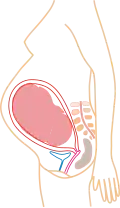

Stadia in beeld

- (aantal maanden refereert aan PML)

6 maanden 7 maanden

7 maanden 8 maanden